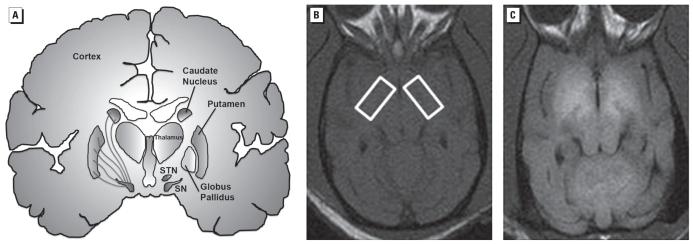

Excess accumulation of manganese (Mn) in the brain results in a neurological syndrome with cognitive, psychiatric, and movement abnormalities. The highest concentrations of Mn in the brain are achieved in the basal ganglia, which may precipitate a form of parkinsonism with some clinical features that are similar and some that are different to those in Parkinson's disease (PD). Recently, scientists have debated the possibility that Mn may have an etiological role in PD or that it may accelerate the expression of PD.

The overwhelming evidence shows that Mn-induced parkinsonism does not involve degeneration of midbrain dopamine neurons and that l-dopa is not an effective therapy. New evidence is presented on a putative mechanism by which Mn may produce movement abnormalities. Confirmation of this hypothesis in humans is essential to make rational decisions about treatment, devise effective therapeutic strategies, and set regulatory guidelines.